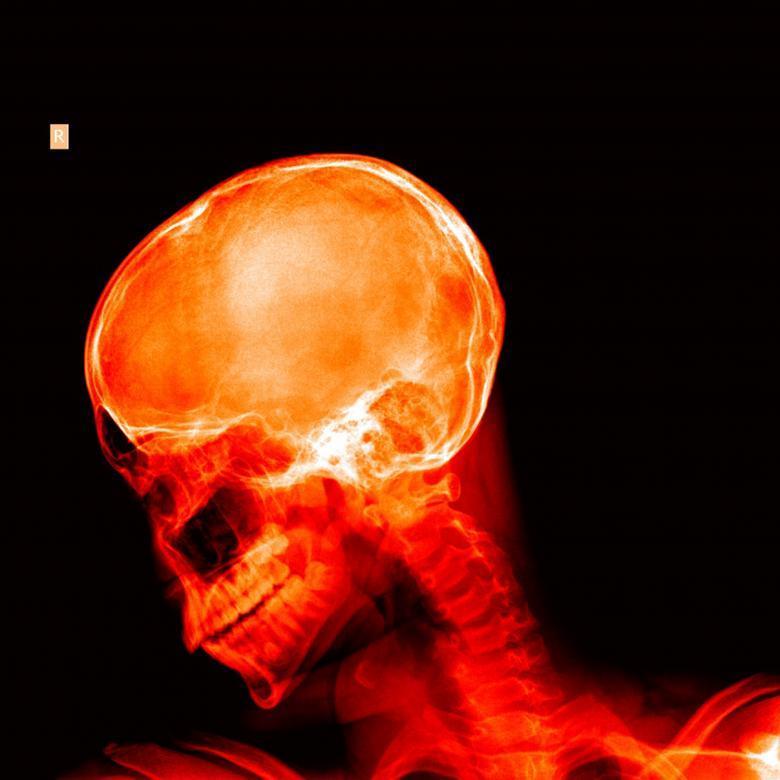

Pourquoi votre chiropraticien pourrait vous recommander des radiographies

Vous consultez un chiropraticien pour une douleur au dos ou au cou. Après avoir discuté de vos symptômes et effectué un examen physique, il vous suggère de prendre des radiographies. Vous vous demandez peut-être pourquoi cet examen est nécessaire et en quoi l'analyse radiologique chiropratique diffère de celle que ferait un médecin.

L'analyse radiologique chiropratique permet d'évaluer non seulement la présence de pathologies, mais également la biomécanique de votre colonne vertébrale. Cette double fonction est unique à la profession. Elle permet au chiropraticien d'adapter précisément ses interventions à votre anatomie spécifique.

L'analyse chiropratique inclut également la recherche de pathologies, mais elle ajoute une dimension supplémentaire : l'évaluation biomécanique. Le chiropraticien analyse l'alignement vertébral, les courbes physiologiques (cervicale, thoracique, lombaire), les asymétries pelviennes, les différences de longueur des jambes, et d'autres paramètres structurels.